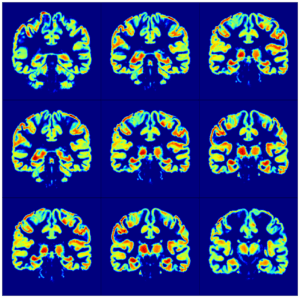

My research integrates advanced neurophysiological and microscopic techniques, with histology and cutting-edge signal processing analysis to explore the fundamental aspects of brain function under health and disease. I focus on cellular communication and network dynamics and interrogate the interplay between intrinsic ionic mechanisms, synaptic transmission and native glial dynamics in relation to physiological and pathophysiological states in neurodegenerative disorders such as multiple sclerosis, Parkinson’s and Alzheimer’s Disease.